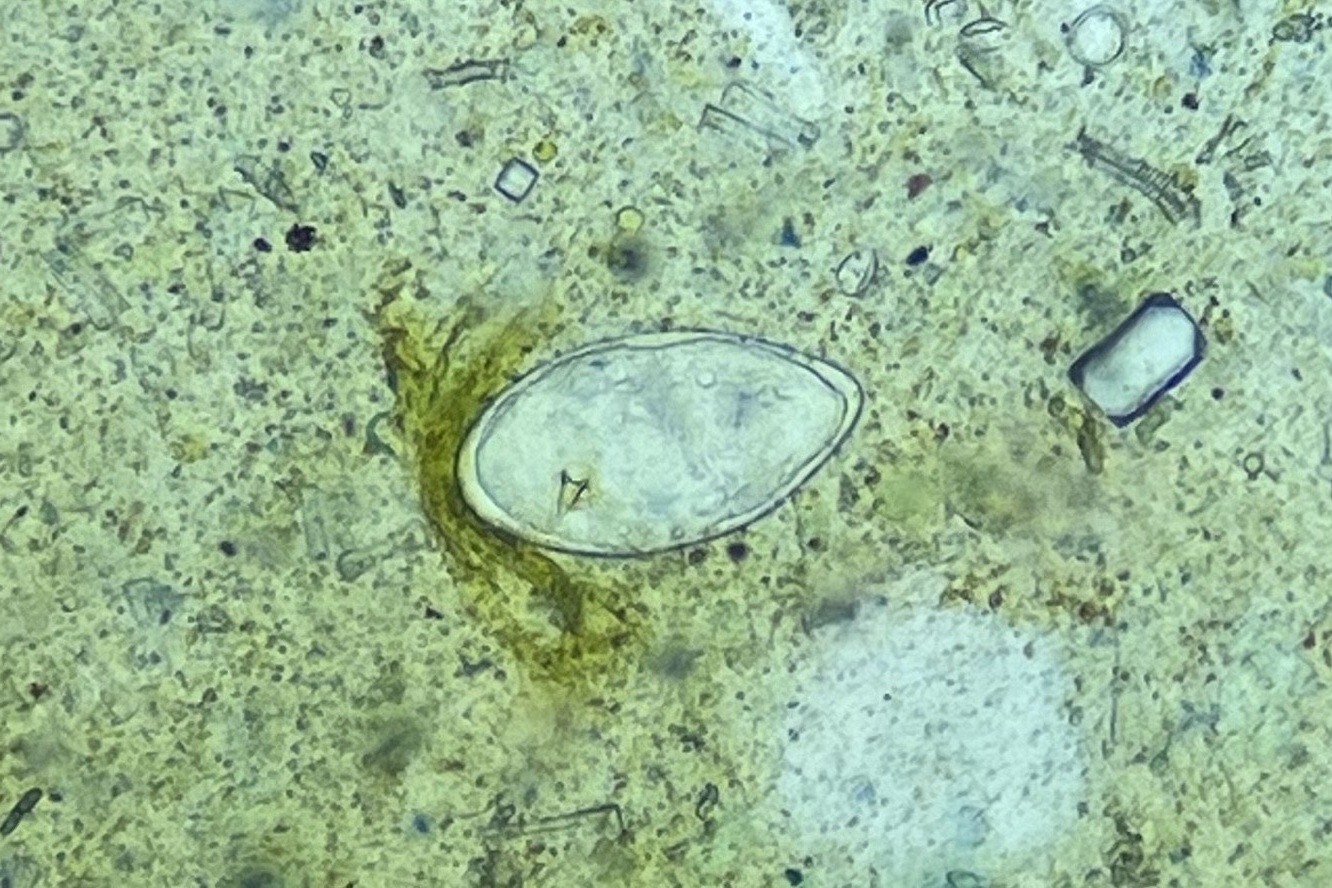

3) 감염성질환 유병률 합동조사

협회 모니터링단은 카메룬 보건부 산하 PLNSHI 연구센터와 함께

중앙주 17개 보건구, 70개교 학생 3,275명을 대상으로

대변 및 소변 검사를 통한 유병률 합동조사를 실시했습니다.

현장 실험실에서는 우리 협회 전문가와 카메룬 보건요원이 함께 검경 작업을 진행하며

전체 대변 검체 3,275건 중 1,917건(54.8%)의 기생충 감염 여부를 분석했어요.

또한 이 조사는 단순한 현장 점검을 넘어,중앙주 전반의 감염 현황을

보건지구 단위로 정밀하게 파악했다는 점에서 중요한 성과를 남겼습니다.

조사 결과, 일부 보건지구에서는

주혈흡충(SCH)과 토양매개성 기생충(STH) 감염이 여전히 높은 수준으로 확인되었으며,

향후 집중 관리가 필요한 고위험 지역을 명확히 식별할 수 있었습니다.